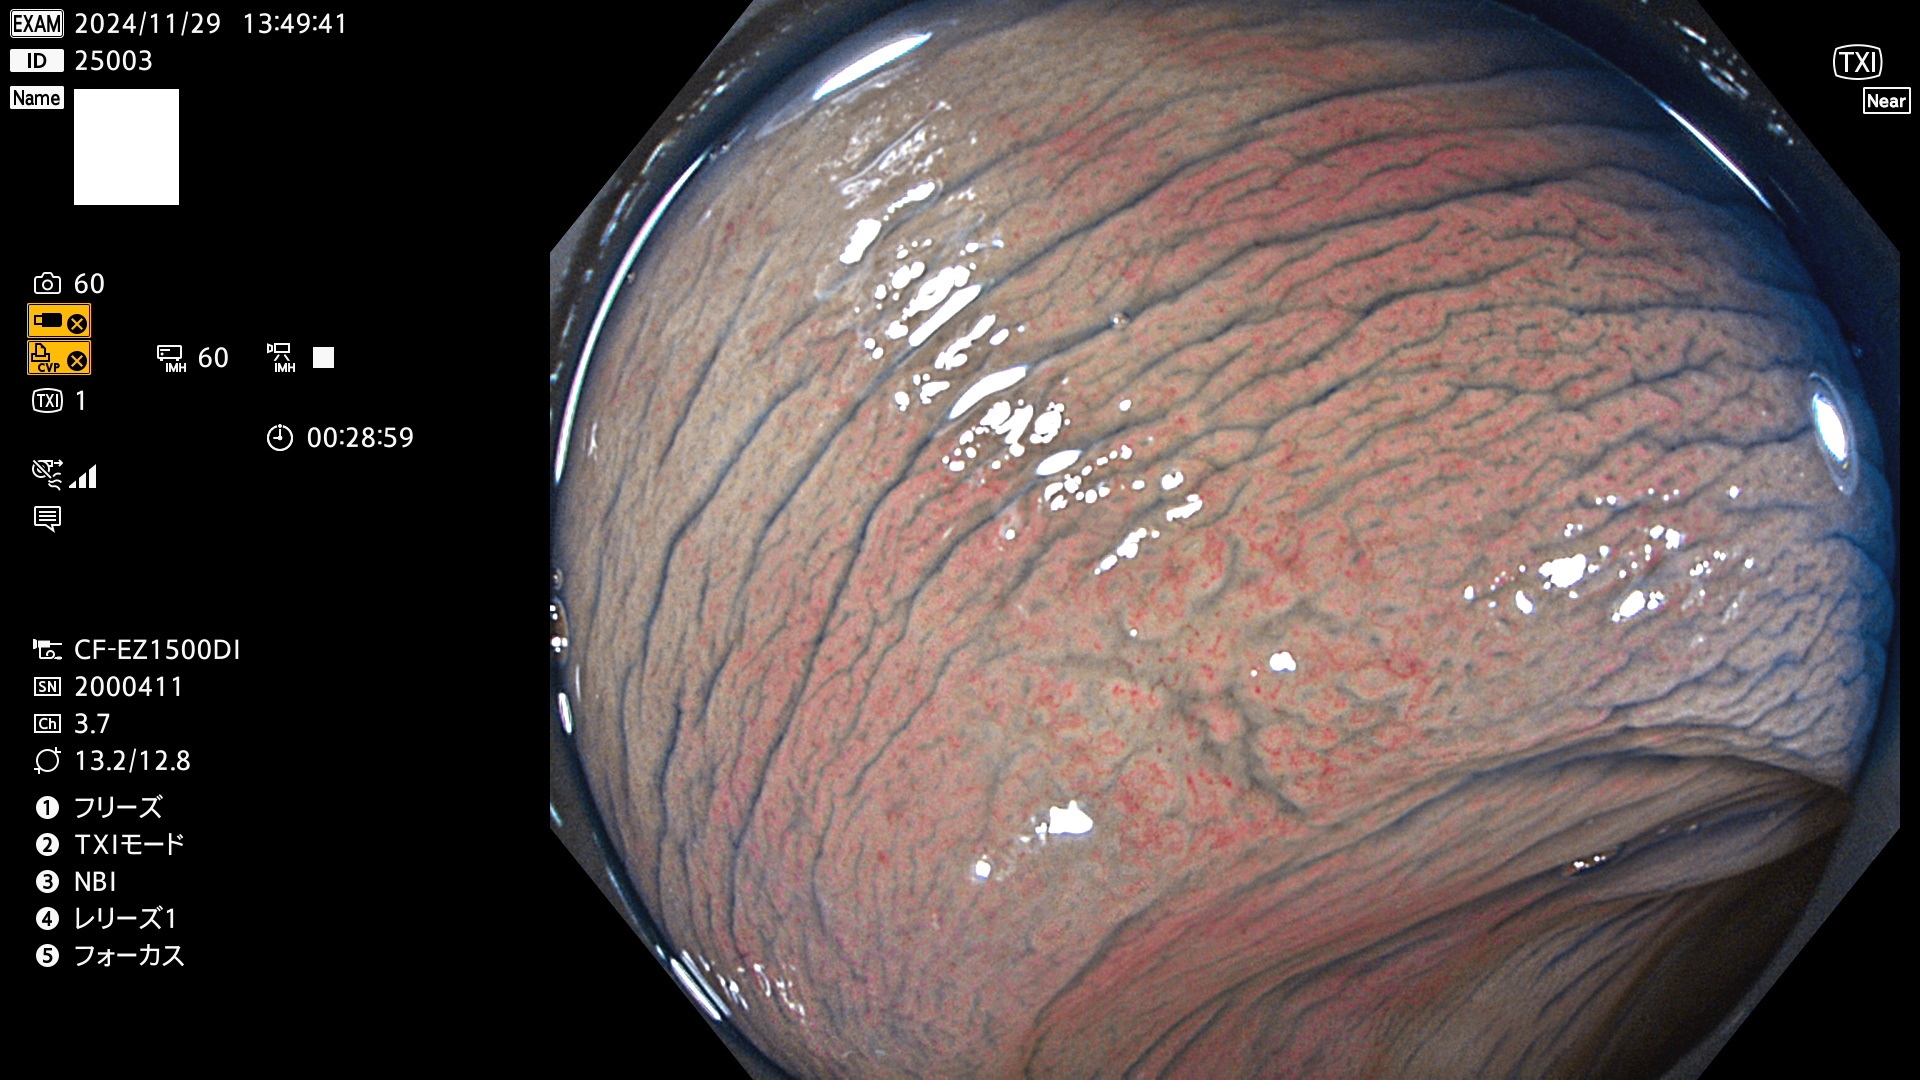

完全に平坦な物をUb、陥凹している物をUcと呼びます。最も発見が難しく危険な病変です。

毎週の検査(木・金・土・日)に発見されたUb、Uc型・腺腫を、その週の日曜の夜にUPし1週間、提示します。

抽出の対象期間 2024年11月28日〜12月2日の5日間(60件の検査)9件 (9/60=15%)